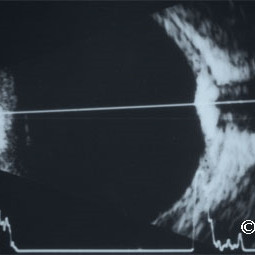

Choroidal hemangioma

Choroidal hemangioma - A-scan reveals high internal reflectivity within the tumor (arrow).